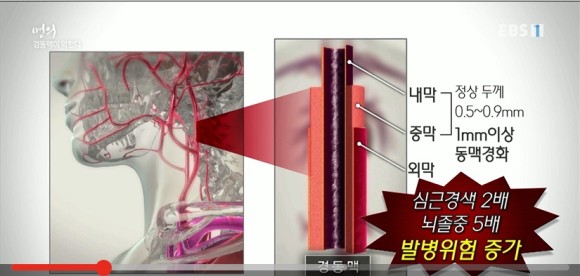

경동맥은 내막, 중막, 외막의 3중으로 되어 있지만 중요한 것은 혈관벽 두께입니다. 건강한 사람은 내막과 중막 두께를 합치면 0.5~0.9mm인데 만약 1mm가 넘으면 찌꺼기가 쌓여 동맥경화 상태로 봐야 합니다. (심근경색의 2배, 뇌졸중의 5배 증가)